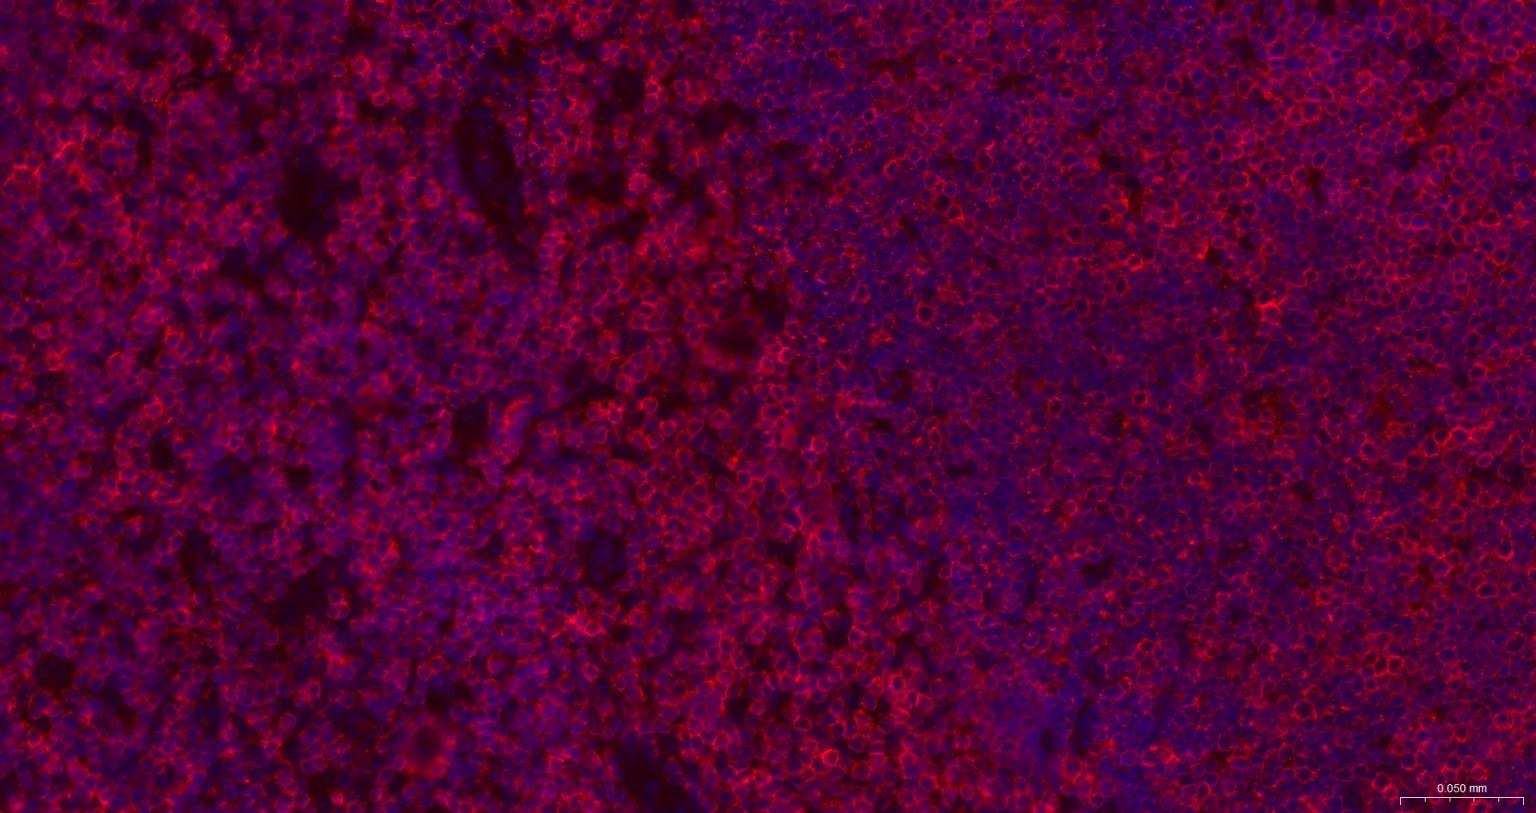

Paraformaldehyde-fixed, paraffin embedded Mouse Spleen; Antigen retrieval by boiling in sodium citrate buffer (pH6.0) for 15 min; The section was incubated with CD3E Monoclonal Antibody, Unconjugated (bsm-60002) at 1:500 overnight at 4°C. Followed by conjugated Goat Anti-Rabbit IgG antibody (Red, bs-0295G-BF594), DAPI (blue, C02-04002) was used to stain the cell nuclei.

Paraformaldehyde-fixed, paraffin embedded Rat Spleen; Antigen retrieval by boiling in sodium citrate buffer (pH6.0) for 15 min; The section was incubated with CD3E Monoclonal Antibody, Unconjugated (bsm-60002) at 1:500 overnight at 4°C. Followed by conjugated Goat Anti-Rabbit IgG antibody (Red, bs-0295G-BF594), DAPI (blue, C02-04002) was used to stain the cell nuclei.